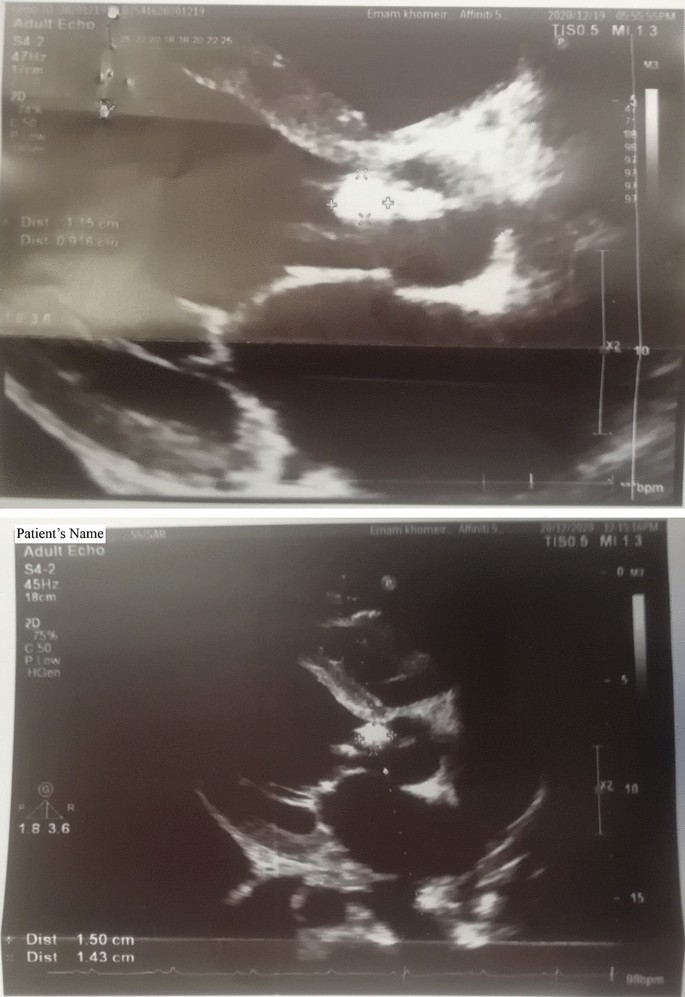

In pre-surgery transesophageal echocardiography (TEE), the left ventricle was severely enlarged with moderate systolic dysfunction, the right ventricle was moderately enlarged with moderate to severe systolic dysfunction, the left atrium was mildly enlarged, the right atrium was enlarged, and mitral valve leaflets were thickened and tethered. No mitral stenosis was observed, but mild to moderate mitral regurgitation was identified. The aortic valve leaflets were thickened and damaged, resulting in mild aortic stenosis and severe aortic regurgitation. A 27 × 13 mm mobile mass was discovered on the right coronary cusp (RCC), suggesting the presence of vegetation (Fig. 1). The tricuspid valve leaflets were tethered, and although there was no tricuspid stenosis, there was severe tricuspid regurgitation. The pulmonary valve leaflets were normal with moderate pulmonic regurgitation and no pulmonic stenosis. A mobile mass measuring approximately 6 × 3.8 mm was connected to the ventricular side of the pulmonary valve, indicating the presence of vegetation.

Echocardiography is essential in diagnosing BCNE. Generally, it confirms the presence of endocarditis, assesses endocardial involvement, and guides treatment decisions56,57. Transthoracic echocardiography (TTE) however, has a limitation in detecting small vegetations, and hallmark lesions of IE, identifying only 25% and 70% of vegetations less than 5 mm, and between 6 and 10 mm57. In contrast, TTE detects 90–96% of the vegetations on native valves regardless of their size58. The size of vegetation in IE can vary depending on the stage of the disease. They may not be visible or very small in the early phases59. A previous study reported that 93.7% of BCNE cases with vegetation of 17.6 ± 11.3 mm were detected using echocardiography60. Our patient presented two large (> 10 mm) lesions simultaneously. A similar rare case was described previously where a patient with infective endocarditis developed vegetative lesions on the pacemaker electrode61. In the present case, the patient had prior antibiotic use, but because he was referred to different physicians it was not possible to track his medication history. Monitoring vegetation size with TTE can be valuable for assessing the effectiveness of antibiotic therapy and predicting the likelihood of complications. This information can assist in making treatment choices and enhancing patient outcomes62. Larger vegetations, also increase the chances of other complications such as heart failure, renal failure, and neurological issues62,63,64.